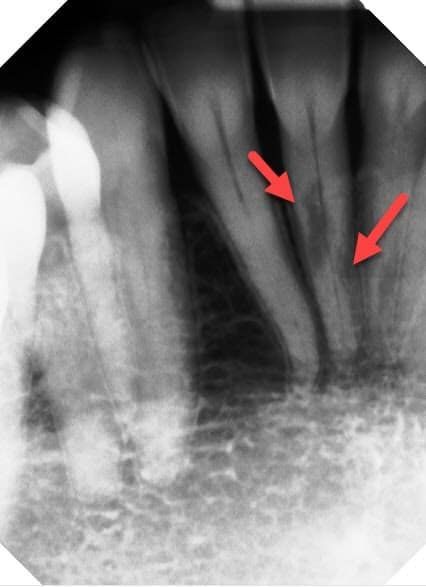

Inflammatory Root Resorption after Braces

There is one type of root resorption that is unfortunately a bit more uncommon. This kind occurs after aggressive tooth movement, and it seems to have a partially genetic basis. This panoramic x-ray is from a long-time patient in our practice. Her roots have gotten progressively shorter over the years, and now they’re starting to get loose. It’s tragic, but she will probably lose all her teeth within the next couple years. That’s why we’re discussing implant-supported bridges to replace all her teeth soon.